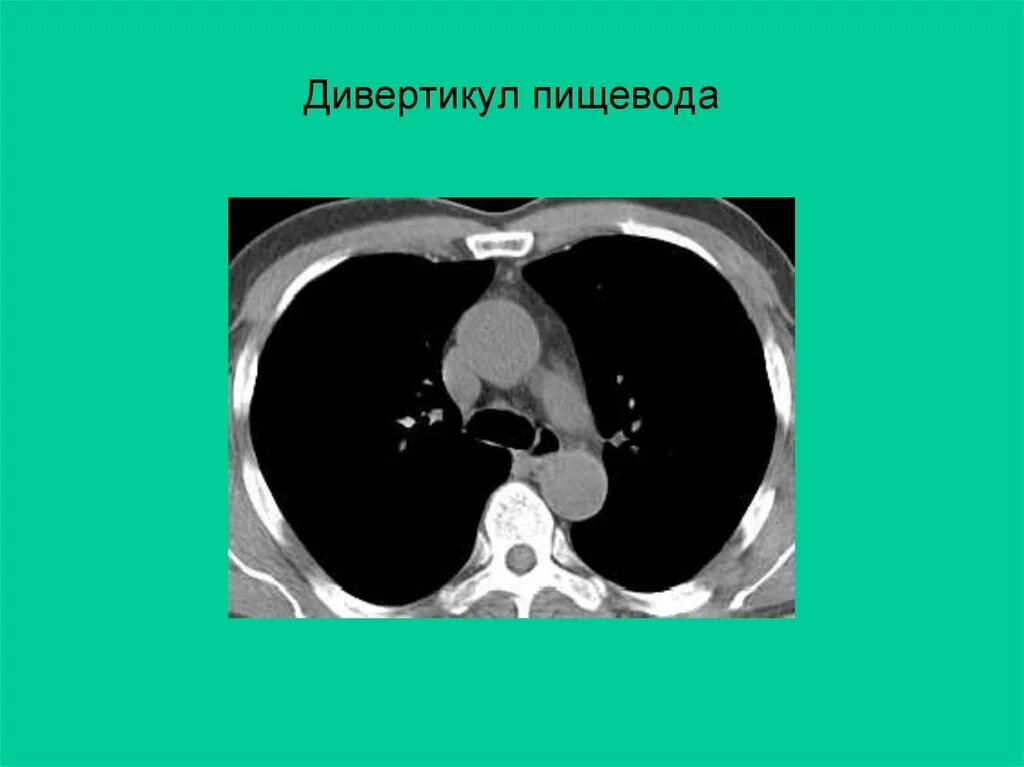

Дивертикул трахеи